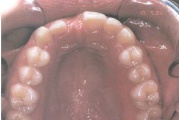

Suulaepoolt lõikunud koonilise kujuga lisahammas

Koonilise kujuga lisahammas ülemiste tsentraalsete lõikehammaste vahel.